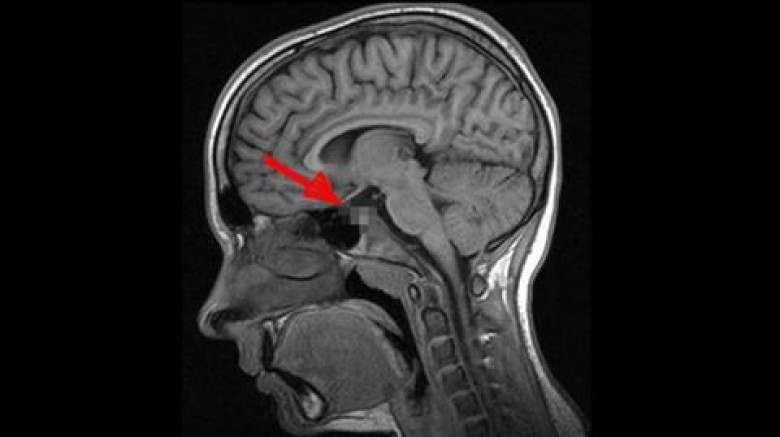

Գիտնականները հայտարարել են, որ ուղեղի այս հիվանդությամբ տառապում է մարդկանց գերակշիռ մեծամասնությունը

Դեժավյուն հոգեբանական կարգավիճակ է, որի ընթացքում մարդուն թվում է, թե նա էլի է հայտնվել նման իրավիճակում: Երևի Ձեզ հետ էլ է պատահել նման բան՝ որևէ անծանոթ տուն կամ վայր առաջին անգամ եք ոտք դրել, սակայն Ձեզ թվացել է, որ այդտեղ արդեն եղել եք:

2009 թ. գիտնականները որոշեցին լրջորեն ուսումնասիրել այս ոչ սովորական երևույթը: Որոշ ժամանակ անց Մասաչուսեթսի տեխնոլոգիական համալսարանի մասնագետները հայտարարեցին, որ ուղեղն ունի այնպսիս հատված, որը պատասխանատու է այս երևույթի համար: Դեժավյուի գլխավոր դերը այն նեյրոններինն է, որոնց շնորհիվ կարողանում ենք զգալ պատկերների ամենափոքր տարբերություններն անգամ: Սրա շնորհիվ մարդը գիտակցում է, թե ինչպիսի տպավորություններ է ինքը վաղուց արդեն ստացել, իսկ որոնք են ամբողջապես նոր նրա համար: Այսն կարծես մարդու «կյանքի փորձառությունը» բաժանում է անցյալի և ներկայի: Սակայն երբ երկու տպավորություններ իրար շատ նման են լինում, ուղեղի այդ հատվածի աշխատանքը «կախում է», ինչն էլ բերում է տարօրինակ այս զագցմանը:

2009թ. բացահայտումից հետո միայն մեկ անպատասխան հարց է մնացել՝ այս երևույթը բնորոշ է առողջ մարդկա՞նց, թե՞ ոչ այնքան: Պատասխանը գտնելու պատասխանատվությունն իրենց վրա վերցրին Չեխիայի Մասարիկա և Մեծ Բրիտանիայի Էկսետերի համալսարանների մասնագետները: Նրանք պարզեցին, որ դեժավյու կարող է լինել անգամ փոքր տարիքում, երբ նոր կազմավորվում է ուղեղը: Հոգնախության և սթրեսի ժամանակ ուղեղի տվյալ հատվածի աշխատանքը խաթարվում է և արդյունքում առաջանում են հիշողություններ այնպիսի բաների մասին, որոնք երբեք չեն էլ եղել: Գիտնականների վերջնական դիագնոզը ցավալի է՝ դեժավյուն համարվում է նյարդաբանական խանգարում: